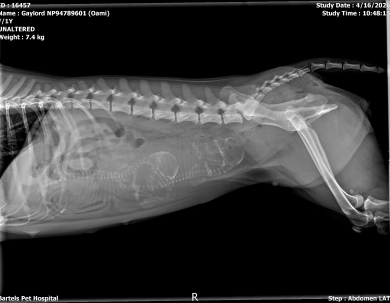

The X-ray shows 2 puppies. Since born on 4/20 this is the \"Up In Smoke\" litter featuring Cheechie and Chong.